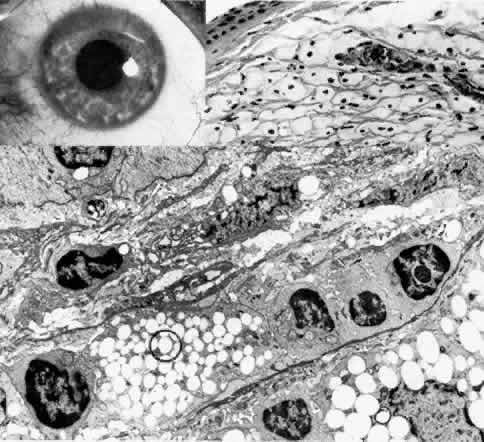

The anterior corneal dystrophies (Fig. 5) are confined to the epithelium, basement membrane, and, in some cases, Bowman's layer.

Fig. 5. Characteristic corneal changes in various types of corneal dystrophy. (Courtesy of A. Bron, MD. Goldberg M: Genetic and Metabolic Eye Disease, pp 283–285. Boston, Little, Brown & Co, 1974)